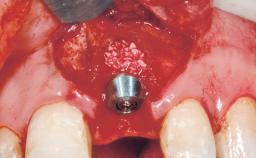

| Placement Protocol | Immediate implant placement |

| Tooth Site | Maxillary incisor or canine |

| Socket Morphology | Single-root socket |

| Socket Integrity | Sufficient, with intact bone walls |

| Bone Volume | Sufficient, with intact walls |